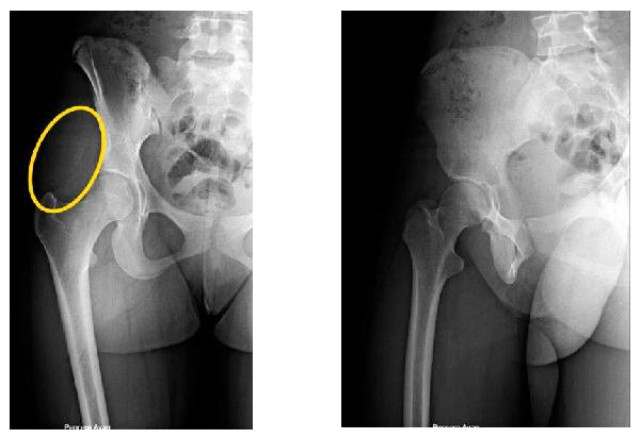

14 yaşındaki ortaokul öğrencisi H.Y. 2017 yılının Şubat ayında karda kayıp düştü. Sert bir şekilde kalçasının üstüne düşen genç kız kalçasında bir ağrı hissetmeye başladı. Eve gittiğinde bir kalem ucu gören genç kız ağrısının nedenini buna bağladı ancak geçmeyince doktora gitti. Röntgen filminde de bir sorun çıkmayan genç kıza doktorlar ağrısının zamanla geçebileceğini söyledi. 15 ay boyunca ağrısı devam edince genç kız birçok hastaneye gitti ve en sonunda İstanbul Üniversitesi Cerrahpaşa Tıp Fakültesi'ne başvurdu. Burada ameliyat edilen genç kızın kalçasından 10 cm uzunluğunda bir kurşun kalem olduğu çıktı. Ameliyatı gerçekleştiren İstanbul Üniversitesi Cerrahpaşa Tıp Fakültesi Öğretim Üyesi Prof. Dr. Nuri Aydın, "Meslek hayatımda böyle bir olaya şahit olmamıştım." dedi.

15 ay boyunca kalçasında bir kurşun kalem ile yaşayan genç kızın doktoru Prof. Dr. Aydın, ameliyatı şöyle anlattı: "Hastamızın oturduğunda ağrısı oluyordu. Daha önce birçok doktora gitmiş ve bu ağrının sebebi anlaşılamamıştı. Çok şiddetli ve bazen geceleri bile uyandıran ağrılar yaşamış. Hastayı muayene ettiğimizde kalem olduğuna dair bir bulgu yoktu ancak hasta buzda düştüğünü ve düşme sırasında kalem ucunun batmış olabileceğini bize ifade etti. Röntgende normalde biz metal cisimleri görebiliyoruz ancak bu bir kurşun kalem olduğu için röntgende çok net bir şey görünmüyordu. Hastanın MR'ını çektik ve orada tümör benzeri bir oluşum gördük. Ne olduğu konusunda bizim de bir fikrimiz olmadı o an ve hastayı ameliyata aldık. Ameliyata aldıktan sonra içeriden Yaklaşık 10 cm uzunluğunda bir kurşun kalemin bütün bir şekilde oraya girdiğini gördük. Açıkçası ben de meslek hayatımda ilk kez böyle bir durumla karşılaştım. Hastadan bu cismi çıkardık ve sağlığına kavuştu."

Hastanın birçok hastaneye başvurduğunu söyleyen Prof. Dr. Aydın, daha önce röntgen ile tanıya gidildiği için tespit edilemediğini söyledi ve "Çok karşımıza çıkan bir durum olmadığı için bu tarz bir batmanın nedeni gözden kaçmış" dedi. Bacakta kurşun kalemin girdiği bölümde önemli sinirlerin de olduğunu belirten Prof. Dr. Aydın, "Eğer o bölgedeki sinirlerden biri hasar almış olsaydı ciddi bir felç durumu olabilirdi. Ancak böyle bir şey yaşanmadı ve hastamız normal bir şekilde sağlığına kavuştu" dedi.